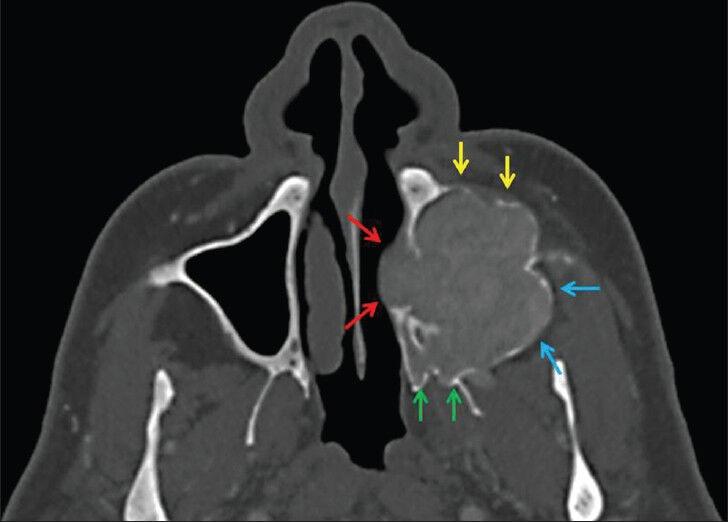

Computed tomography findings of an unusual maxillary sinus mass: brown tumor due to tertiary hyperparathyroidism.

Brown tumor is a non-neoplastic bone lesion that develops secondary to hyperparathyroidism and it is very rare in the maxillofacial region. We report the case of a 59-year-old man who presented with pain and a swelling in the left cheek. Computed tomography (CT) demonstrated an expansile and radioluscent lesion in the left maxillary sinus. Incisional biopsy was performed, and the diagnosis was Brown tumor. Brown tumor must be considered in the differential diagnosis of expansile lesions of maxillary sinus.

棕色瘤是一种继发于甲状旁腺功能亢进的非肿瘤性骨病变,在颌面部区域非常罕见。我们报告一例59岁男性患者,其左侧脸颊出现疼痛和肿胀。计算机断层扫描(CT)显示左上颌窦有一个膨胀性、透光性病变。进行了切开活检,诊断为棕色瘤。在上颌窦膨胀性病变的鉴别诊断中必须考虑棕色瘤。